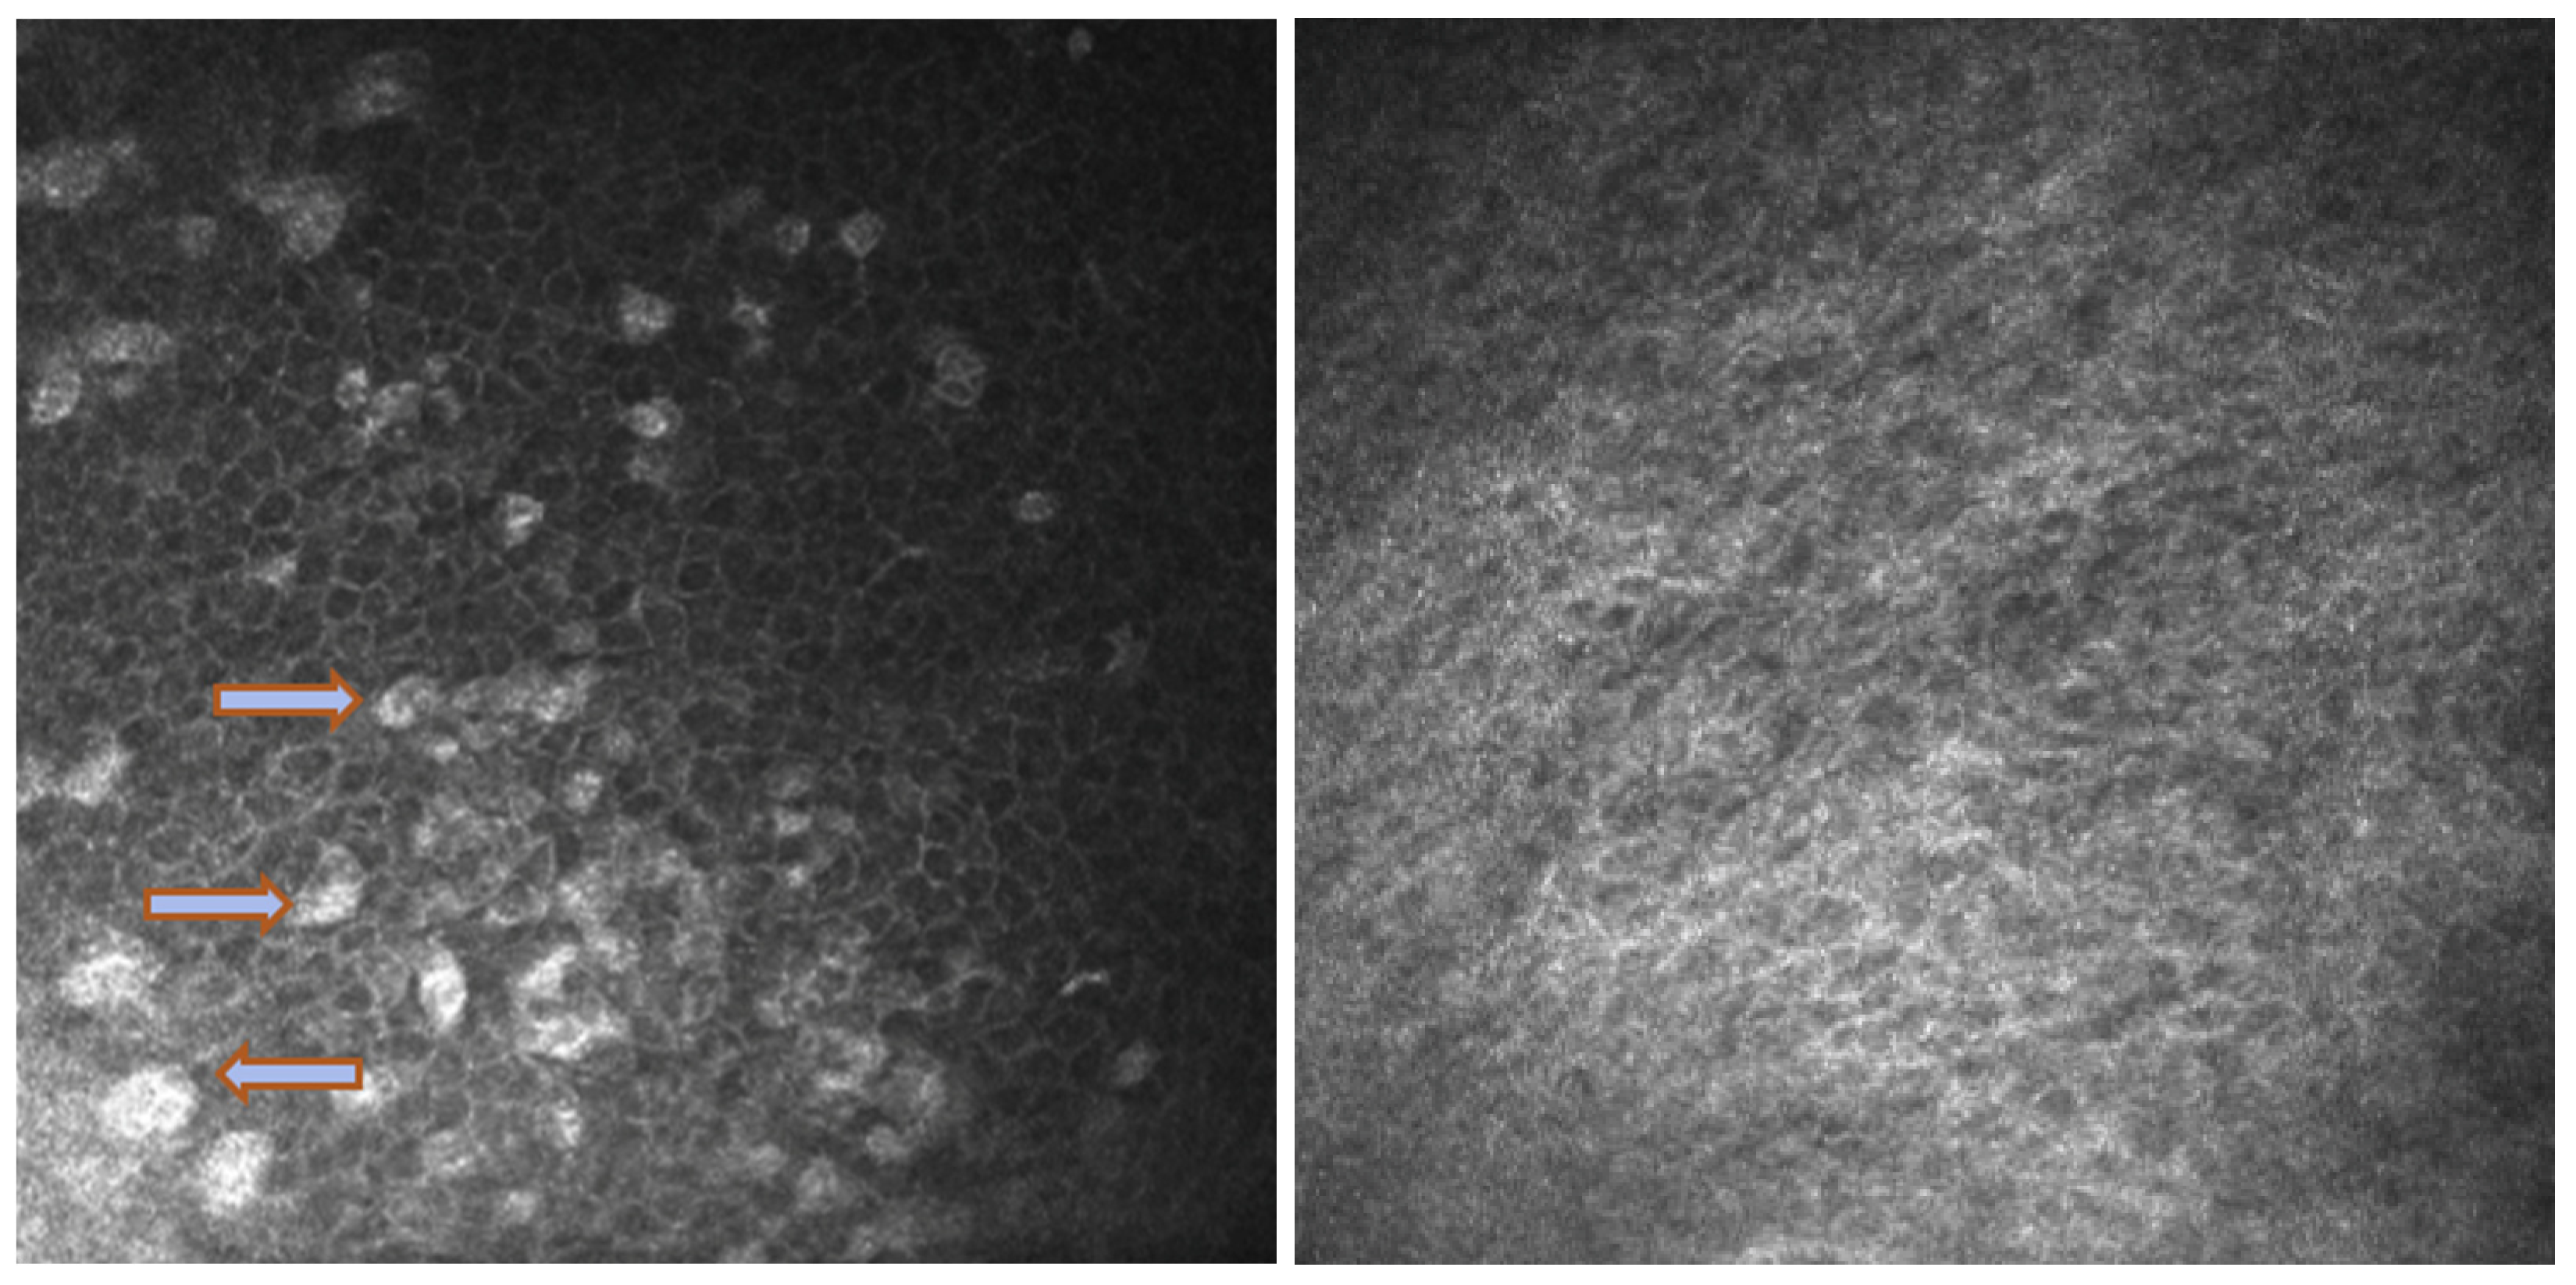

Among the naive group, three patients (27%) were symptomatic for ocular discomfort. In Group 2, sixteen patients (73%) presented with symptoms of ocular surface disease as itching or dry eye (Figure 1), but only seven patients of sixteen with symptoms (32%) reported worsening conditions after beginning Dupilumab injections (Table 3). No patients have developed sight-threatening complications, such as symblepharon and ocular surface keratinization. None discontinued the therapy because of the ocular side effects.

Figure 1. Color images of the eye in a case of Dupilumab-related conjunctivitis in Group 2: four quadrants of bulbar vessels are strongly dilated.